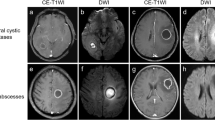

Contrast-enhanced magnetic resonance imaging (MRI) is the first choice for the screening, diagnosis, and treatment of BM patients. The contrast enhancement caused by media extravasation is attributed to the increased vascular permeability with the exchange of contrast media between different compartments since the capillary permeability of metastases is higher than that of healthy tissues [8]. However, the imaging manifestations of different types of BM on the traditional 3 min enhanced images are similar, thereby making the pathological types undistinguishable [9, 10]. Serres et al. [11] confirmed the difference in growth pattern and angiogenesis of metastases among different primary tumour types through mouse experiments, with metastases from lung cancer and melanoma showing poor and rich blood supply, respectively [12, 13]. The difference in the angiogenic ability of different pathological type metastases and that in the heterogeneity between tumour cells and blood vessels will cause different dynamic changes in the contrast media over time, which will be displayed on delayed images [14].

The mean grey level of all metastases in 189 patients were 1403.0, 1467.0, 1457.9, 1419.4, 1387.6, and 1375.5 at 1, 3, 5, 10, 18, and 20 min, respectively, and the peak grey level was observed at 3 min. Compared with that at 3 min, the grey level at 1, 5, 10, 18, and 20 min decreased by 4.6%, 0.6%, 3.4%, 5.7%, and 6.7%, respectively, and the mean grey level showed a downward trend as time progressed. There was a significant difference between the maximum and minimum grey level (P < 0.05), as shown in Figs. 4 and 5.

Contrast-enhanced MRI revealed that vascular permeability is related to tumour aggressiveness, and a marked increase in signal intensity in contrast-enhanced areas is a diagnostic criterion for BM [27]. There are significant differences in the heterogeneity of tumour cells and blood vessels following metastasis in different pathological types of primary tumours, and the penetration of contrast media into a tumour is time dependent. Therefore, we propose that multi-phase delayed enhancement can reflect the dynamic change in the contrast medium dispersion in BM. However, previous studies on MR radiomics for BM pathology prediction have only used conventional static timing of 3 or 5 min [28].